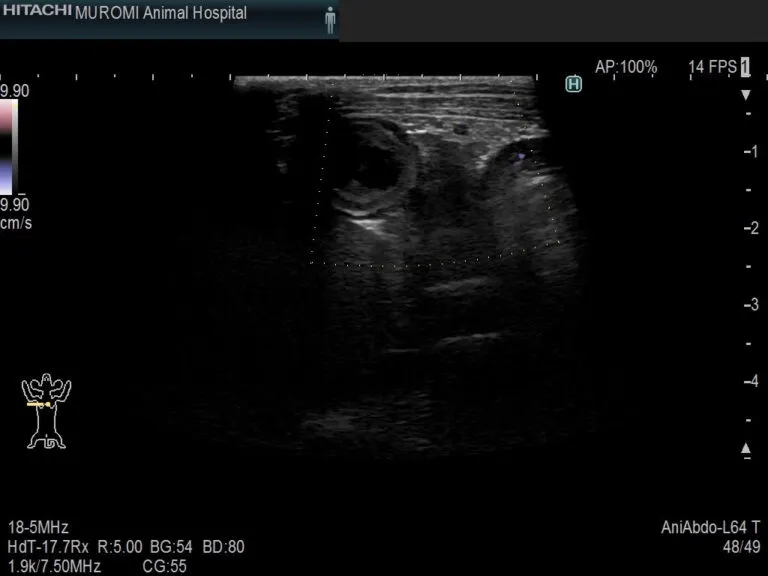

◎腹部エコー検査・・・膵臓や周囲の組織、その他腹腔内の状態を確認します。

膵臓エコー画像